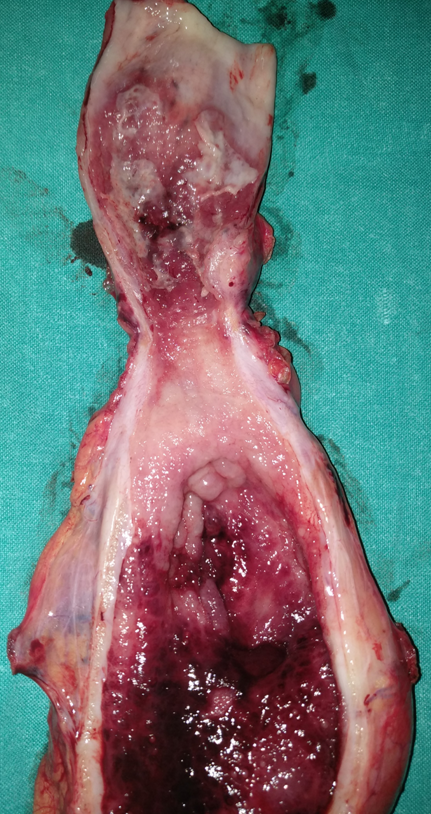

Duodenectomy sparing Vater s papilla .Poorly differentiated adenocarcinoma invading full thickness the duodenal wall and surrounding fatty tissue with clear cut margins (Courtesy Dr. V. Penopoulos)